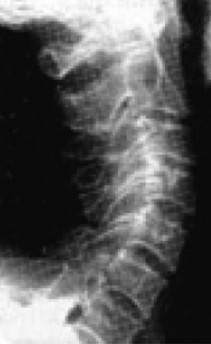

Причем, опять же, рост этого горбика она объясняет исключительно «солями» – остеохондрозом – и не связывает с изменившейся статикой своего позвоночника. В норме позвоночник, как известно, не должен быть прямым, как палка, а иметь физиологические изгибы. В частности, шейный отдел, состоящий из 7 позвонков, в норме должен быть чуть прогнутым внутрь (рис. 13).

Рис. 13. Нормальная статика шейного отдела

Рис. 13а. Спрямление шейного отдела

Рис. 13б. Гиперлордоз шейного отдела